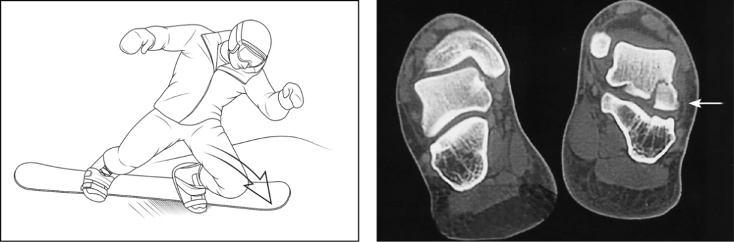

图二、典型的滑雪板骨折机制——CT:距骨骨折

图源:《Comprehensive Review of Skiing and Snowboarding Injuries》